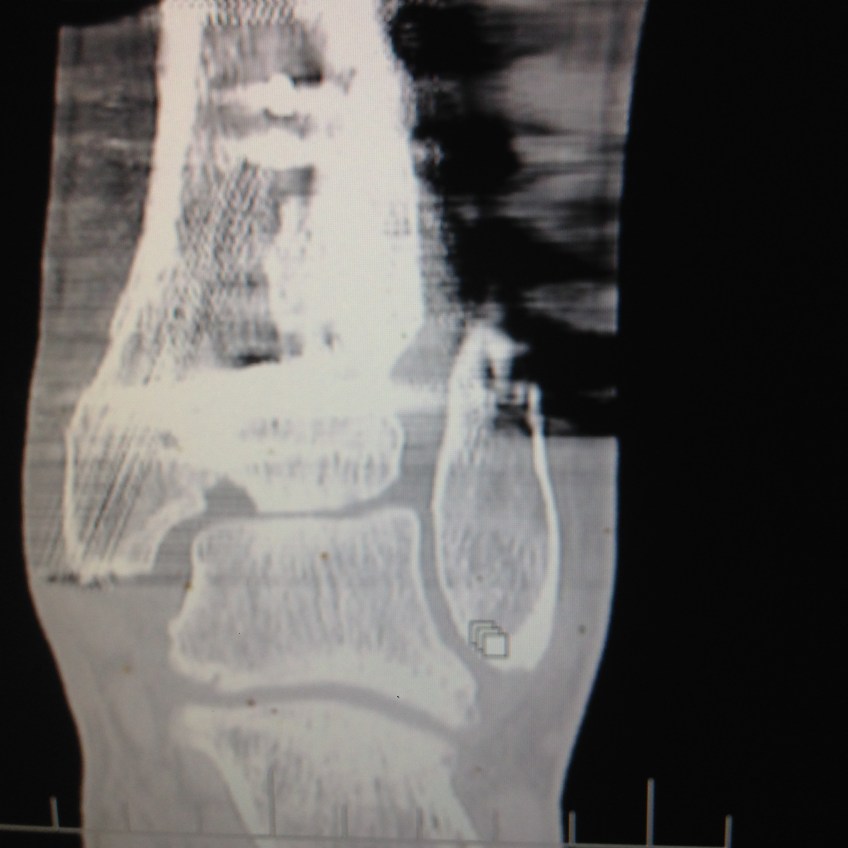

2015-12-03 09.16.17 Published December 6, 2015 at 2448 × 2448 in Ankle replacement not an option, Fusion needs to wait too